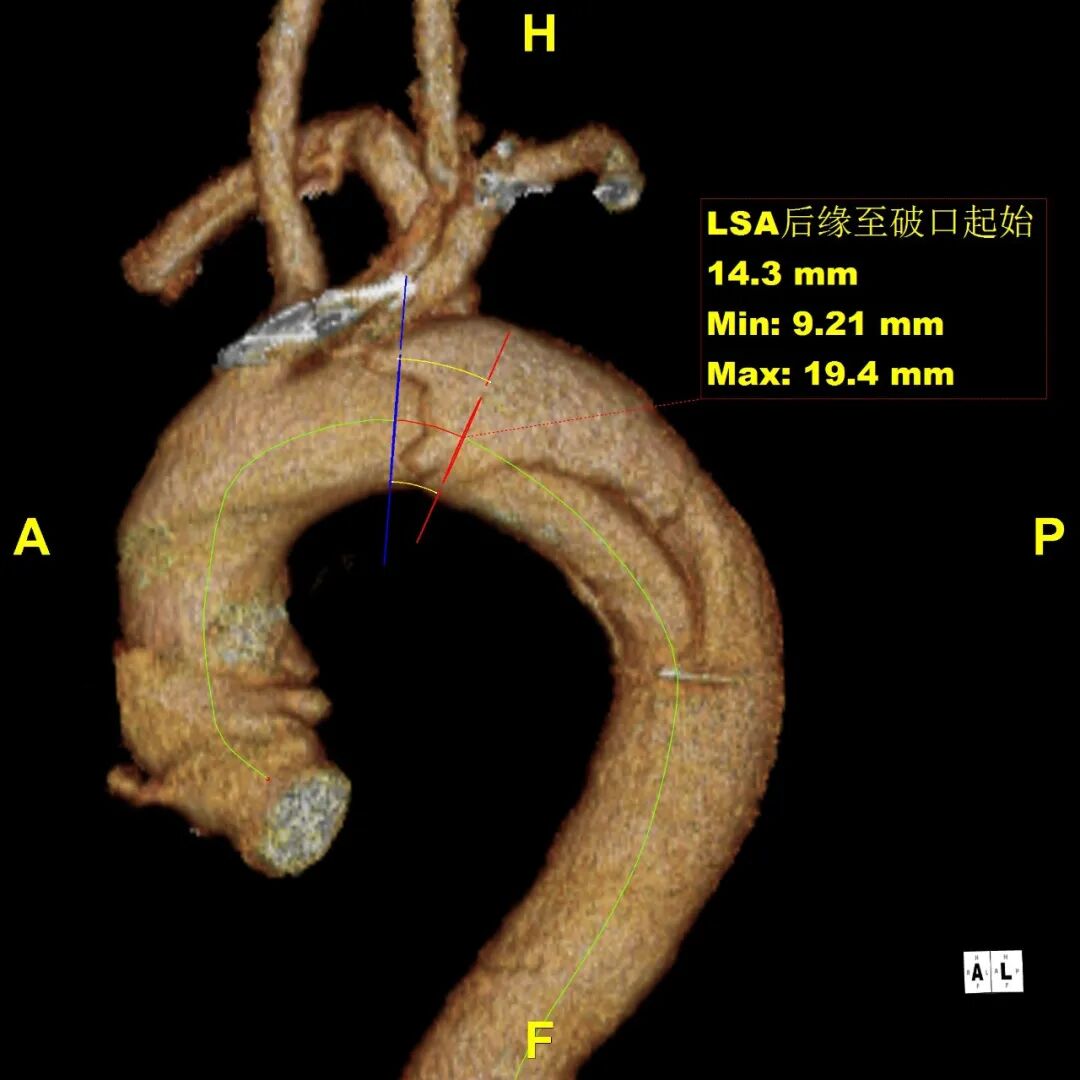

患者 10月前因“梗阻性黄疸、胆总管结石”检查发现主动脉夹层B型,否认腹痛、腰背痛,追问病史,2019年曾出现胸痛,行冠脉造影未见异常,当时血压170mmHg。诊断为:B型主动脉夹层累及到LSA后缘,左侧椎动脉发自于主动脉弓上的变异解剖形态

正位造影:左椎动脉起至主动脉弓,弓上四分支显影好,双侧椎动脉显影,左前55度造影:自左锁骨下动脉开口5mm处降主动脉可见小破口,标记左颈总、左锁骨下动脉,破口、小弯侧拐角。交换Lunderquist导丝并控制血压到100mmHg,导入20F鞘,导入GORE® TAG® 可主动调控胸主动脉覆膜支架(31-31-200mm)到靶病变,将支架覆膜开始部分定位于左锁骨下动脉开口中段释放,经造影评估后,微调支架位置和小弯侧贴附后,二次拉线释放。最后,造影显示降主动脉血流通畅,支架形态好,支架完全封堵原发破口,左颈动脉血流通畅,左锁骨下动脉通畅,未见内漏。